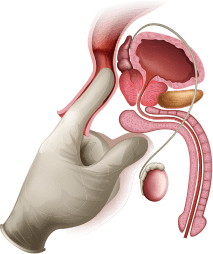

proceduri umilitoare

28.573 bărbați

recomandă

clinic

Conform statisticilor oficiale, fiecare al doilea

bărbat cu vârsta peste 20 de ani este bolnav de prostatită

cronică.

Demonstrat:

Cifre reale, conform părerii experților:

85% din bărbați cu vârsta peste 20 de ani suferă de prostatită

cronică.

Odată pătrunse în organism,

componentele active

încep să acționeze practic

instantaneu, eliminând durerea

și inflamația la nivel celular,

calmând spasmele musculare, îndepărtând

trombii și vindecând mucoasa.

Componentele formulei active

restabilesc lumenul îngustat

al uretrei.

Se normalizează golirea regulată și completă a

vizicii urinare,

uitând de vizitele nocturne la WC,

fără durere și disconfort.

Celulele afectate și organele

tractului urinar își recuperează

funcțiile naturale.

Este restabilită circulația

sanguină din regiunea glandei prostata.

Viața sexuală revine la normal.

Rezultatul este fixat pentru o lungă perioadă de timp.